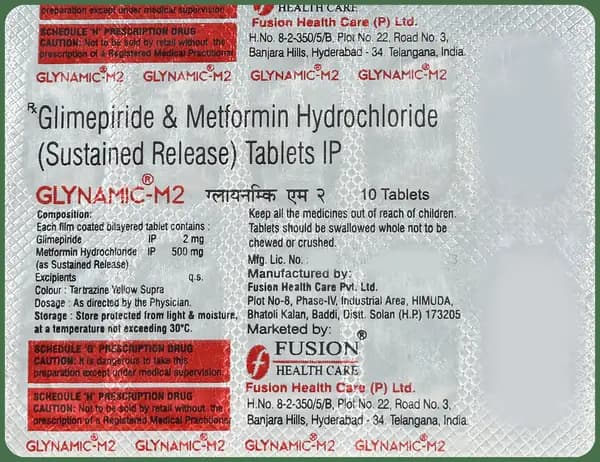

Glynamic M 2mg/500mg Tablet

Fusion Healthcare Pvt Ltd

Composition

Metformin500mg+1

₹91₹113

Get Substitute at 80% Cheaper

Glynamic M 2mg/500mg Tablet

Fusion Healthcare Pvt Ltd

₹

91113Rx Required